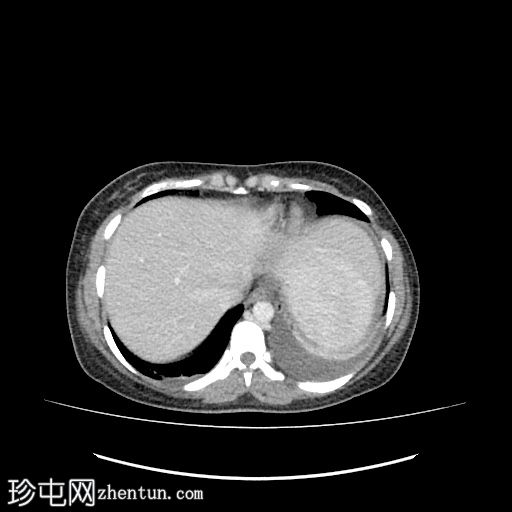

轴位

平扫

肝下区可见一大小约15 x 15.2 x 8.6 cm的较大、边界清晰、呈不均匀强化的实性肿块。

该病灶压迫胃小弯、幽门和胃窦,并对肝脏产生占位效应。门静脉和下腔静脉受压,但脂肪间隙保持完整,未见明确的血管侵犯。

肿块左侧可见正常的胰尾。胰管未见扩张。

肝内胆管和胆总管管径正常。

腹主动脉旁可见亚厘米级淋巴结,最大者短轴直径为 3.5 mm。

中度弥漫性腹水,少量左侧胸腔积液。